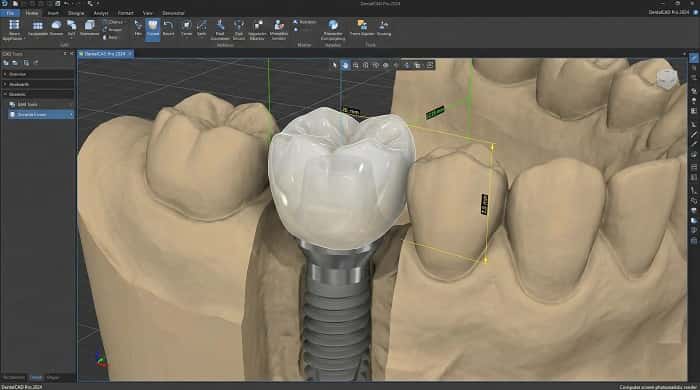

نقش لابراتوار تخصصی دیجیتال در طراحی و ساخت پروتز ثابت ایمپلنت

کیفیت نهایی پروتز ثابت روی ایمپلنت به کیفیت طراحی و ساخت لابراتواری وابسته است. لابراتوار تخصصی دیجیتال با استفاده از اسکنهای سهبعدی، طراحی CAD و ساخت CAD/CAM میتواند فیت، مسیر اینسرت، ضخامت متریال و مسیر پیچ را با دقت بالا کنترل کند. هماهنگی علمی بین دندانپزشک و لابراتوار، از مرحله انتخاب نوع پروتز تا انتخاب متریال، نقش مهمی در کاهش ریمیک و افزایش طول عمر ترمیم دارد.

برای آشنایی بیشتر با نقش لابراتوار در زنجیره درمان، مطالعه مروری بر دندانپزشکی دیجیتال و نقش لابراتوار و نیز معرفی لابراتوار تخصصی دیجیتال میتواند دید جامعتری ارائه دهد.

در عین حال، طراحی مسیر پیچ، زاویه دسترسی و محل خروج پیچ از نظر زیبایی و فانکشن باید بهدقت در مرحله طراحی CAD و لابراتواری مدیریت شود.

زیرکونیا مونولیتیک و لایهای

زیرکونیا بهعنوان متریالی با استحکام بالا و بیوکامپتیبیلیتی مناسب، در پروتز ثابت روی ایمپلنت کاربرد گستردهای پیدا کرده است. در ساختارهای مونولیتیک، کل روکش یا بریج از بلوک زیرکونیا طراحی و میلینگ میشود و سپس رنگآمیزی و گلیز میگردد. در نوع لایهای، روی زیرکونیای زیرساخت، سرامیک ونیر برای افزایش شفافیت و زیبایی اعمال میشود. انتخاب بین این دو به موقعیت دندان (قدامی یا خلفی)، سطح نیرو، و انتظارات زیبایی بستگی دارد.